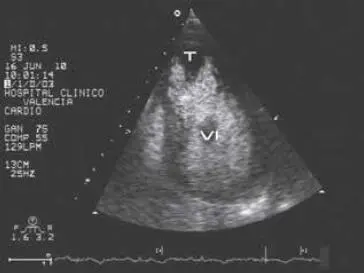

Fig 212 Imagen bidimensional del ventrículo izquierdo obtenida desde la - фото 26

Fig. 2.12 Imagen bidimensional del ventrículo izquierdo obtenida desde la posición apical tras la inyección de ecocontraste. Se ha opacificado la cavidad ventricular izquierda y en su zona apical se observa un defecto de replección originado por un trombo intraventricular. Abreviaturas: T = trombo; VI = ventrículo izquierdo.